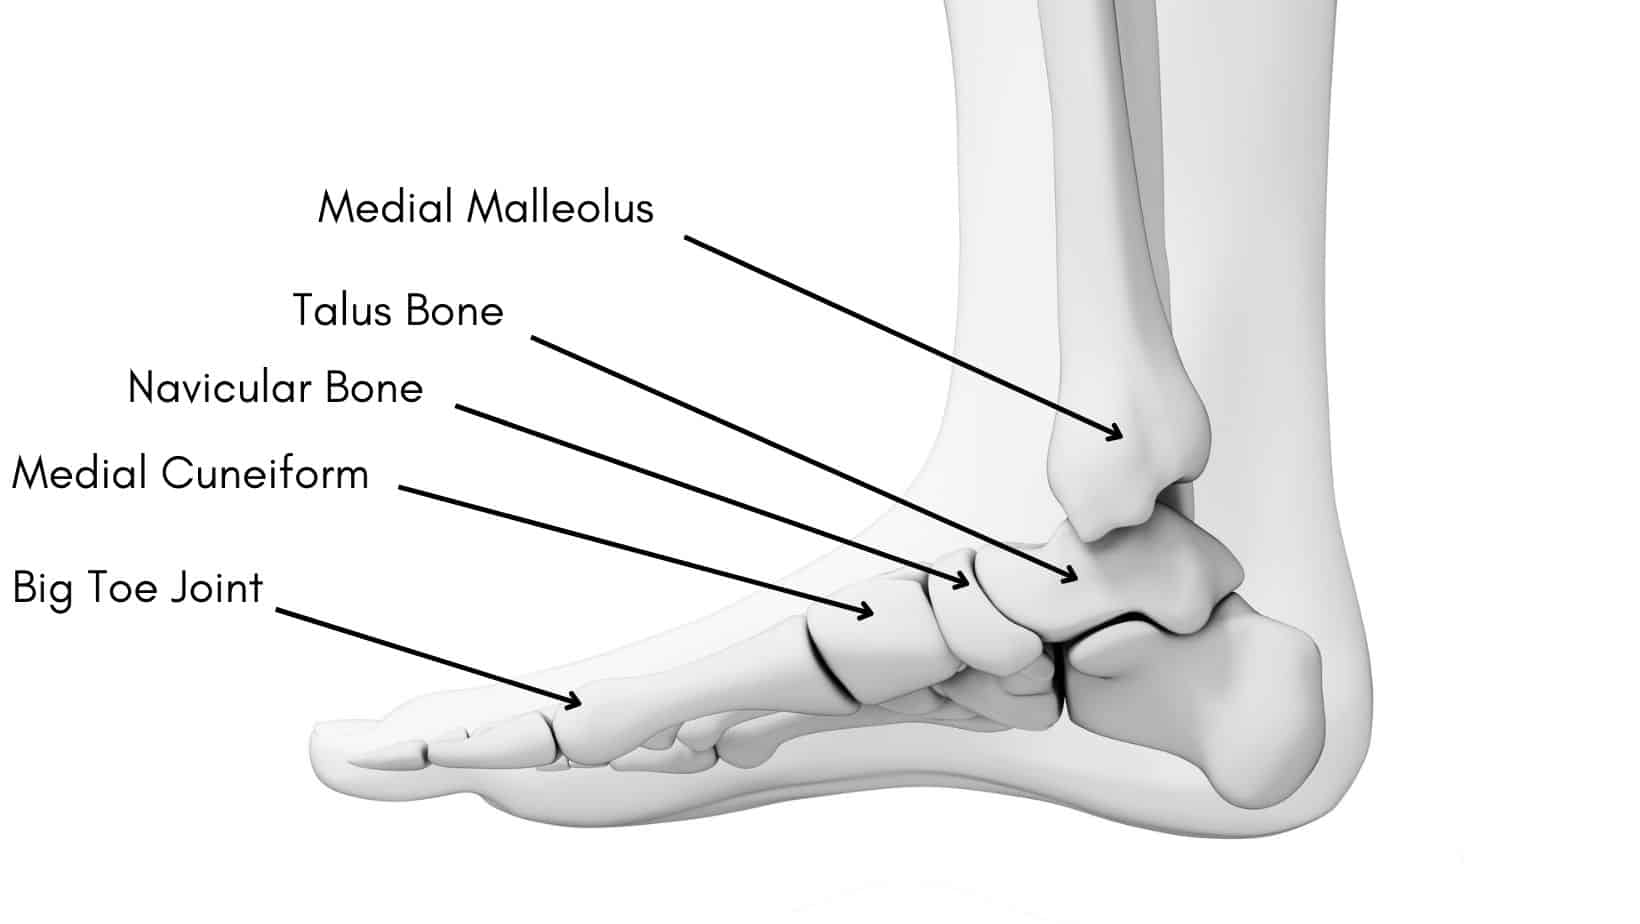

12. Rhinelander FW. Tibial blood supply in relation to fracture healing. Clin Orthop Relat Res. 1974:34–81. [PubMed] [Google Scholar]

21. Richards RR, Schemitsch EH. Effect of muscle flap coverage on bone blood flow following devascularization of a segment of tibia: an experimental investigation in the dog. J Orthop Res. 1989;7:550–8. [PubMed] [Google Scholar]

22. Richards RR, McKee MD, Paitich CB, Anderson GI, Bertoia JT.

A comparison of the effects of skin coverage and muscle flap coverage on the early strength of union at the site of osteotomy after devascularization of a segment of canine tibia. J Bone Joint Surg Am. 1991;73:1323–30. [PubMed] [Google Scholar]

23. Richards RR, Orsini EC, Mahoney JL, Verschuren R. The influence of muscle flap coverage on the repair of devascularized tibial cortex: an experimental investigation in the dog. Plast Reconstr Surg. 1987;79:946–58. [PubMed] [Google Scholar]